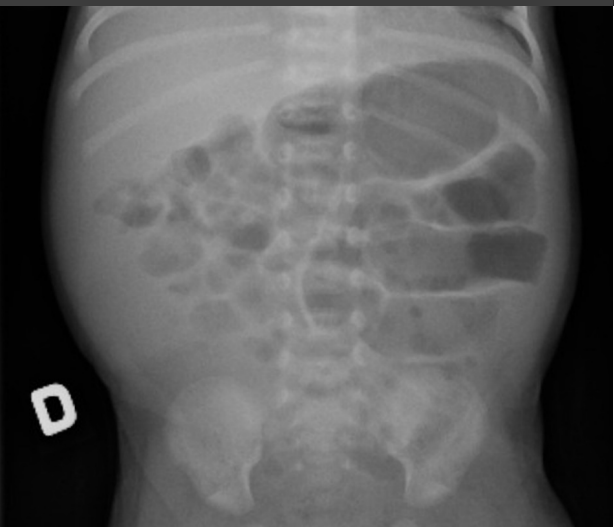

- Atresia Duodenal: Falha na recanalização do lúmen intestinal. Sinal da Dupla Bolha. Alta associação com Síndrome de Down. Cirurgia: Diamond Shape.

- Estágio I (Suspeita): Distensão, resíduo gástrico, sangue oculto. Rx normal ou íleo leve.

- Estágio II (Definida): Sangue visível nas fezes, acidose, plaquetopenia.

- Sinal Radiológico: Pneumatose Intestinal (gás dissecando a parede da alça) ou gás no sistema porta.

- Estágio III (Avançada/Perfurada): Choque séptico, CIVD, peritonite.

- Sinal Radiológico: Pneumoperitônio (gás livre).